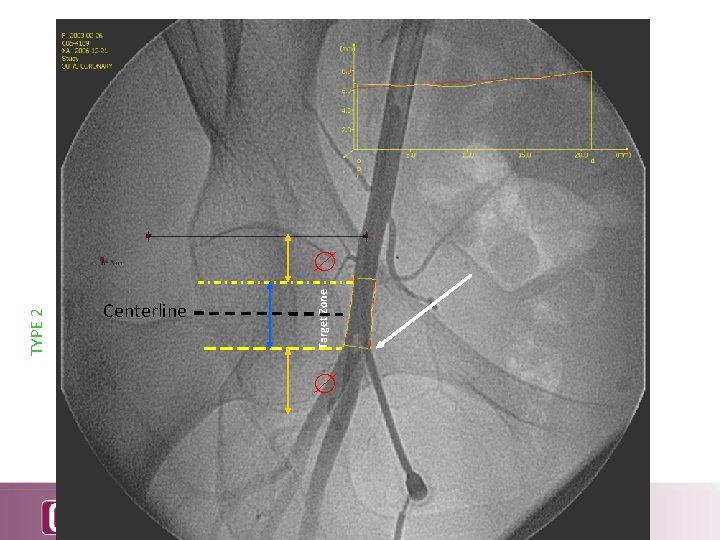

TYPE 2 Centerline Target Zone

Cumulative Probability of Being Outside Target Zone Above FH Centerline Below